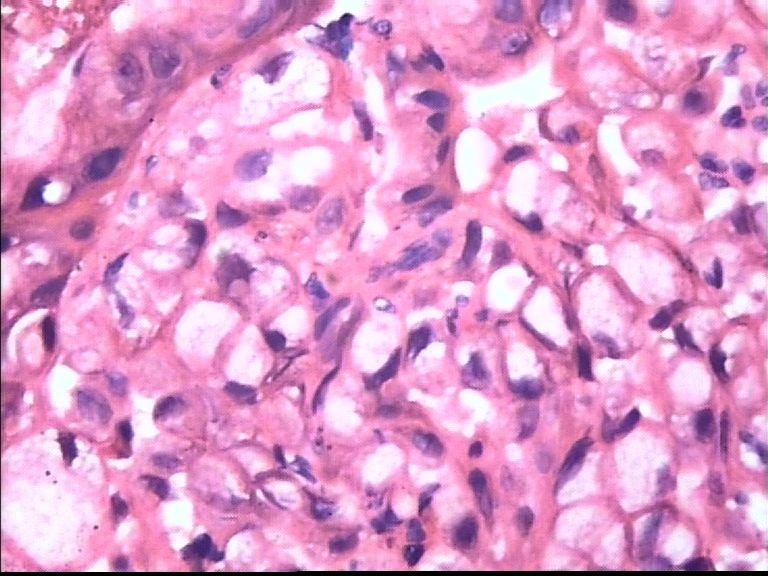

胃部溃疡3cm 53岁 男

仅此局部形态,应该是印戒细胞癌,最好有更多的背景资料

印戒细胞癌

倾向印戒细胞癌

诊断印戒细胞癌

印戒细胞癌高度可疑,建议做:CK、CD68、PAS帮助诊断。